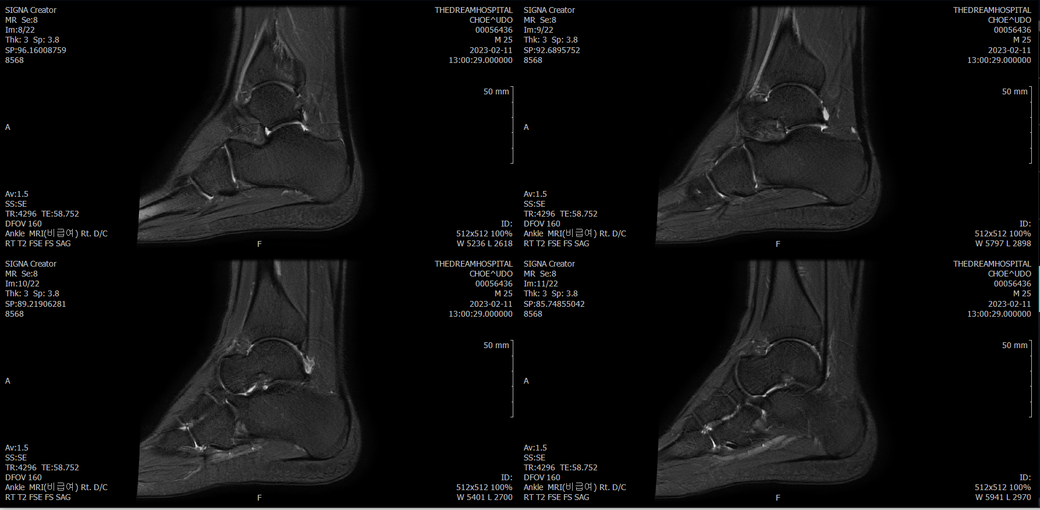

오른발목 mri 전체사진입니다. 제가 병원을 갈수없는상황인지라.... 봐주시면 감사하겠습니다.

엑스레이에서는 문제가 없다고 하여 오른발목 mri촬영했습니다.

우선 전반적으로 봤을 때 큰 이상은 없어보입니다.

전거비인대 등도 저명한 손상은 없는 것 같아 보이지만, 어느 부분의 통증 등으로 인해 촬영을 하셨는지 말씀을 해주신다면 보다 정확한 병변파악이 가능하겠으며, 병원에서 판독이 완료되신다면 전화 등으로 문의를 해보시는 것이 좋겠습니다.